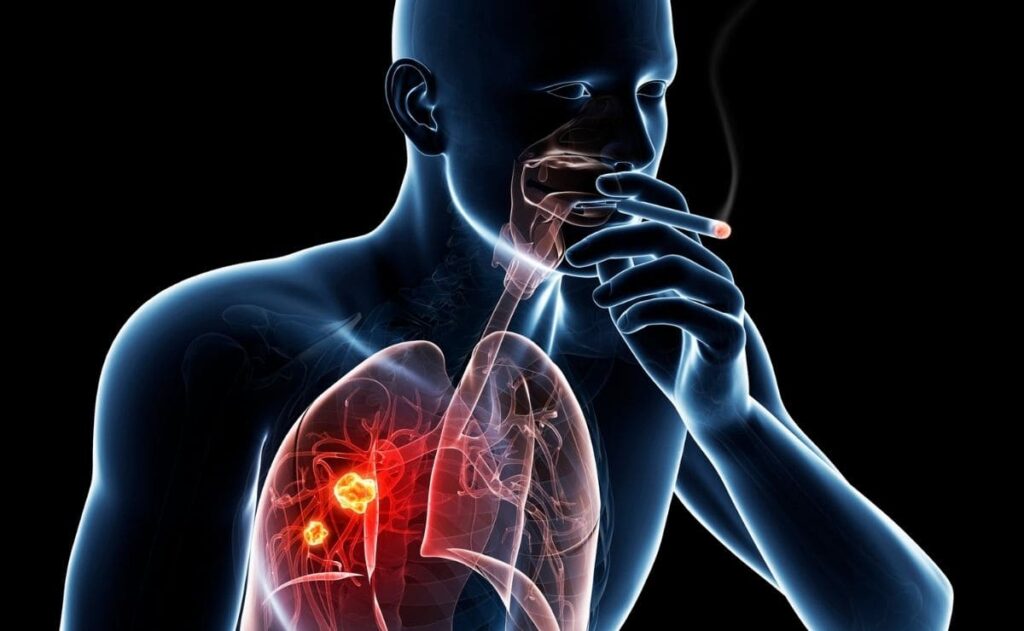

El cáncer pulmonar se considera una enfermedad del hombre moderno. Su causa principal es el consumo de tabaco. La neoplasia es rara

antes de los 40 años de edad, y las tasas aumentan hasta los 80 años, cuando vuelve a disminuir.

Los fumadores de cigarrillos tienen un riesgo de 10 veces o más de presentar cáncer pulmonar en comparación con personas que nunca han fumado. El riesgo de cáncer pulmonar es menor en personas que abandonan el hábito que entre quienes lo continúan; los exfumadores tienen un riesgo nueve veces mayor de presentar cáncer de pulmón que los varones que nunca fumaron, frente a un exceso de 20 veces entre quienes persisten en su hábito.

La disminución del riesgo aumenta con el tiempo que ha transcurrido desde que la persona dejó de fumar, a pesar de que, en general, incluso quienes dejaron de fumar hace mucho tiempo tienen mayor riesgo de cáncer pulmonar que quienes nunca fumaron. El tabaquismo agrava el riesgo de padecer todos los tipos principales de cáncer pulmonar.

Otra causa definida de cáncer pulmonar es el humo del tabaco ambiental llamado también tabaquismo pasivo. El riesgo por el tabaquismo pasivo es menor que el del tabaquismo activo.